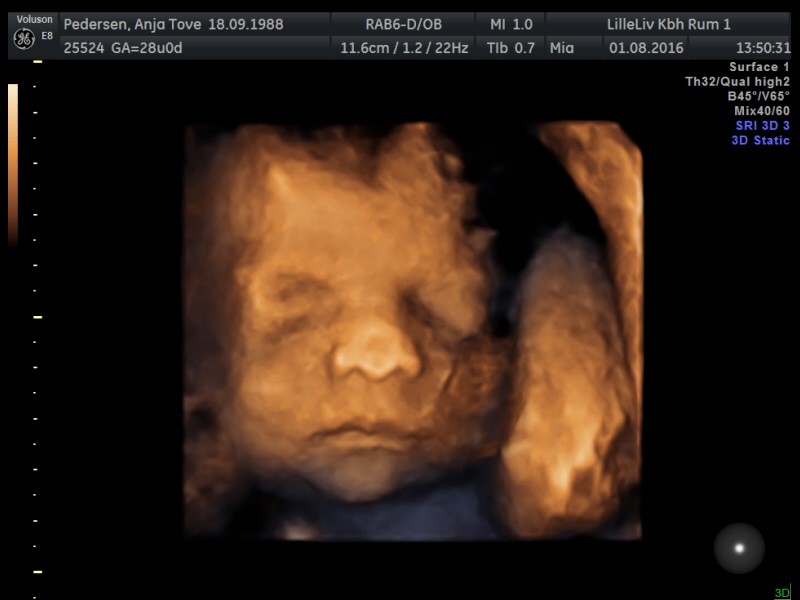

Vi har valgt gaver fra til hinanden og i stedet tog vi til 3D/4D skanning for at se til prinsessen

Hvilken fantastisk oplevelse! Hun startede med at have foden i hovedet, men hun var dog lidt sød og lagde sig anerledes så vi kunne se hendes smukke ansigt

Og nej hvor hun ligner sin far! Og dermed ligner hun altså også Isaac virkelig meget, ingen tvivl om hvem hverken far eller storebror er!

Billeder af maven bliver ikke denne gang, men af prinsessen i 3D